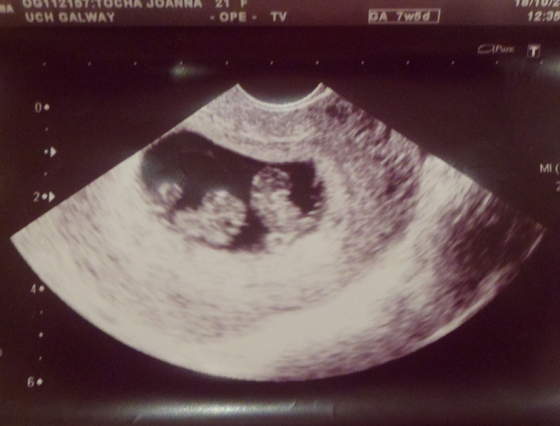

Dzięki dziewczyny. Maluszek machał do nas faktycznie, tylko nie wiem do kogo - do mnie, tatusia czy do pana doktora

. A najważniejsze że krwiak się wchłania. Biorę jeszcze Duphaston, ale jest już dużo lepiej.

. A najważniejsze że krwiak się wchłania. Biorę jeszcze Duphaston, ale jest już dużo lepiej.Dreddka, a Ty się nie martw. Twój maluszek będzie równie piękny, a nawet powiem, że dla ciebie napewno piękniejszy, bo swój zawsze jest wyjątkowy